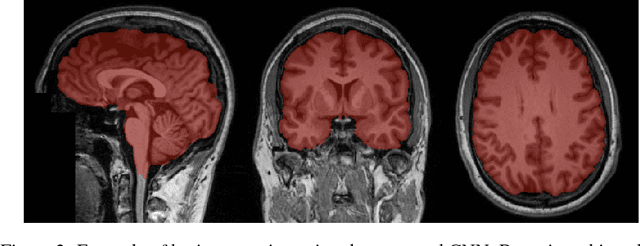

Abstract:Skull-stripping methods aim to remove the non-brain tissue from acquisition of brain scans in magnetic resonance (MR) imaging. Although several methods sharing this common purpose have been presented in literature, they all suffer from the great variability of the MR images. In this work we propose a novel approach based on Convolutional Neural Networks to automatically perform the brain extraction obtaining cutting-edge performance in the NFBS public database. Additionally, we focus on the efficient training of the neural network designing an effective data augmentation pipeline. Obtained results are evaluated through Dice metric, obtaining a value of 96.5%, and processing time, with 4.5s per volume.